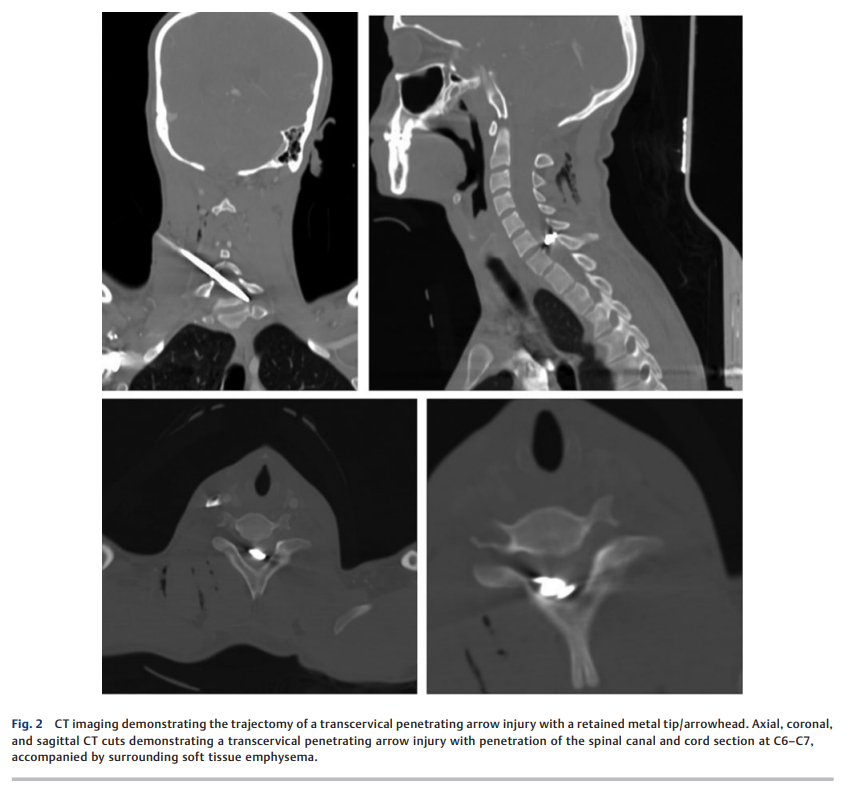

Chelmis FS et al.

穿透性脊髓损伤中的箭伤病例极为罕见。由于箭体邻近重要神经血管结构且箭头形态各异,箭头的取出颇具挑战性。本研究结合临床经验与现有文献,着重探讨此类损伤的最优治疗方案。